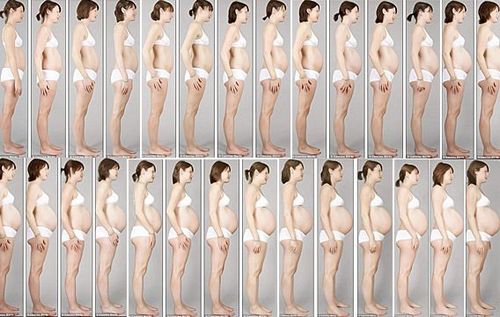

ЯК ВИГЛЯДАЄ ЕМБРІОН В КАРТИНКАХ

(35 тиждень вагітності) натисніть для збільшення